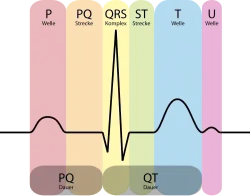

Elektrokardiogramm

Das EKG ist eine nicht-invasive Untersuchungsmethode, bei der die elektrische Aktivität der Herzmuskulatur mit Elektroden abgeleitet wird. Es gibt im Wesentlichen drei verschiedene Formen, die bei der Diagnose einer chronischen KHK von Bedeutung sind. Das Ruhe-EKG ist Bestandteil der Basisdiagnostik. Belastungs-EKG und Langzeit-EKG werden in Abhängigkeit vom Risikoprofil des Patienten und der Vortestwahrscheinlichkeit durchgeführt.

Ruhe-EKG

Das Ruhe-EKG gehört zur grundlegenden internistischen Diagnostik, nicht nur bei Verdacht auf eine koronare Herzkrankheit. Für einen sicheren Nachweis einer chronischen KHK ohne bisher abgelaufenen Herzinfarkt ist das Ruhe-EKG allerdings eher ungeeignet. Es kommen Zeichen zur Darstellung, die für einen abgelaufenen Infarkt oder auch eine Verdickung des Herzmuskels im Rahmen einer Bluthochdruckerkrankung sprechen. Im Weiteren können Herzrhythmusstörungen wie Vorhofflimmern oder häufige Extraschläge (ventrikuläre Extrasystolie) gesehen werden, die ebenfalls ein indirektes Zeichen für das Vorliegen einer KHK sein können.[4]

Belastungs-EKG

Langzeit-EKG

Ist der Befund des Belastungs-EKGs negativ, es besteht jedoch weiterhin die Verdachtsdiagnose chronische KHK, kann ein Langzeit-EKG sinnvoll sein. Insbesondere für das Aufdecken stummer Ischämien kann es hilfreich sein. Ein positives Testergebnis liegt mit hoher Wahrscheinlichkeit vor, wenn wiederholt ST-Streckensenkungen auftreten, die länger als 1 Minute andauern.[1] In der Praxis wird das Langzeit-EKG für diese Indikation eher selten verwandt.